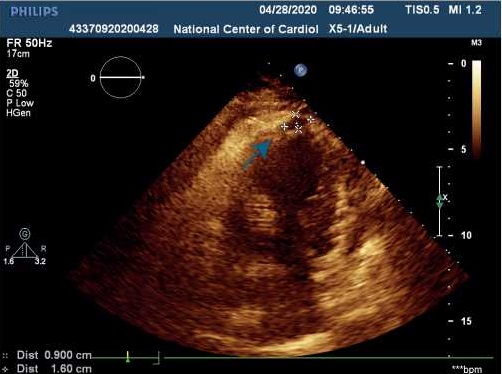

Несмотря на принимаемые меры лечения, состояние пациентки оставалось тяжелым, на фоне кардиогенного шока отмечались признаки острого почечного повреждения (скорость клубочковой фильтрации составила 17 мл/мин/1,73 м 2 ), острой энцефалопатии. По данным трансторакальной эхокардиографии (ЭхоКГ) сердца (табл. 1) на фоне акинеза среднего и апикального сегментов межжелудочковой перегородки, передней и боковой стенок левого желудочка (ЛЖ) с захватом верхушки ЛЖ, отмечалась сепарация листков перикарда в диастолу — 1,2 см за задней и боковой стенками ЛЖ, у верхушки — 0,8 см за счет наружного разрыва миокарда. Вся полость перикарда заполнена отложениями фибрина умеренной эхогенности. В области верхушки со стороны полости ЛЖ лоцировался дополнительный эхосигнал (пристеночный тромб) размером 2,7х1,6 см, под которым визуализировалось эхонегативное пространство размером 1,6х0,9 см (место разрыва миокарда) (рис. 4, 5). Кровоток через место разрыва миокарда не определялся.

Рис. 4. Трансторакальная ЭхоКГ пациентки Б.

Примечание: апикальная 2-х камерная позиция: сепарация листков перикарда в диастолу — 1,2 см за задней и боковой стенками ЛЖ, у верхушки — 0,8 см за счет наружного разрыва миокарда, под ним эхонегативное пространство размером 1,6х0,9 см (место разрыва миокарда).

Сокращение: ЛЖ — левый желудочек.